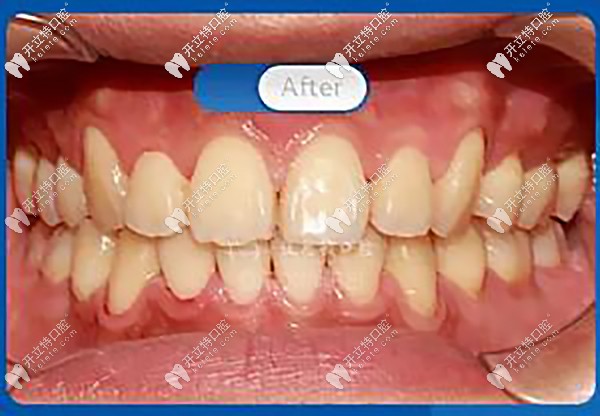

歷經(jīng)24個(gè)月終于完成了矯正,快看看我的變化吧!

正面看,內(nèi)收前牙,排齊牙列、牙中線,解除磨牙深覆蓋,恢復(fù)正常咬合關(guān)系。

笑容自信陽(yáng)光有感染力